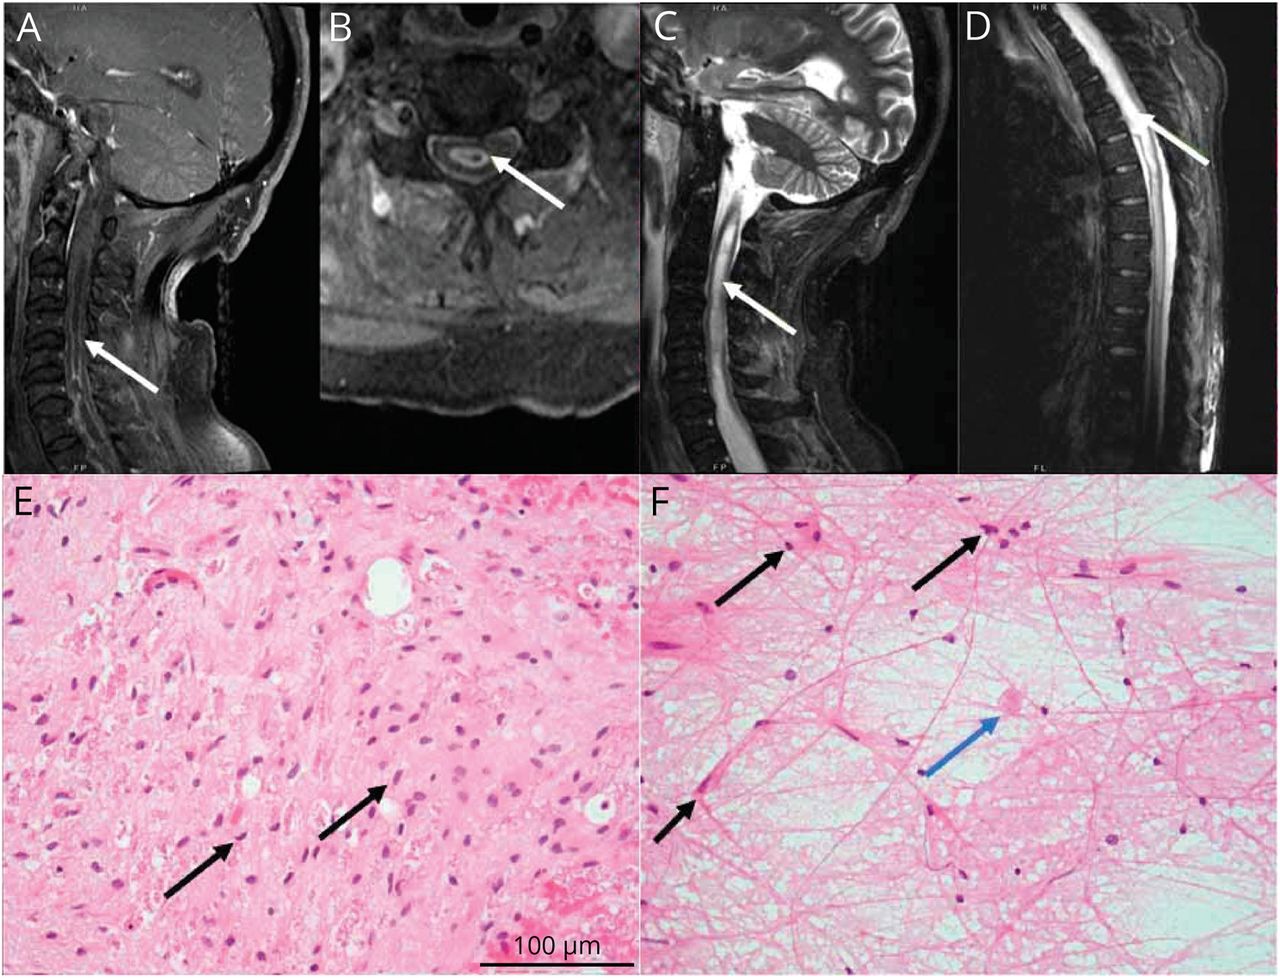

一个68岁的男人没有病史发达的进步的软弱和cervicalgia 2个月。检查显示与T10感官层面的四肢瘫痪。脊柱MRI显示obex的膨胀性的髓内病变与周围结节性增强(T11图中,模拟)。大脑核磁共振、全身PET / CT和广泛的血清诊断是正常的(eTable 1,links.lww.com/WNL/C653)。脑脊液显示蛋白质2505 mg / dL, 0细胞/μL葡萄糖88 mg / dL,脑脊液细胞游离DNA测序中分离出一种致病变种叔p。神经胶质瘤C250T,可疑。1胸脊髓切片是追求排气可逆的病因和显示浸润神经胶质瘤叔启动子突变(图中,E和F)。由于进行性四肢瘫痪、呼吸衰竭,预后差,护理是为了安慰。

脊柱MRI显示一个扩大的,髓内T2 hyperintense信号异常,与周边结节增强跨越C4-T5 (A, B)和纵向广泛扩张T11 obex的中央管(C, D)。)部分在400×放大显示浸润神经胶质瘤与适度多形性,深染细胞与piloid流程(E, F黑色箭头)和偶尔的嗜酸性颗粒体(F,蓝色箭头)。他走时=苏木精和伊红。